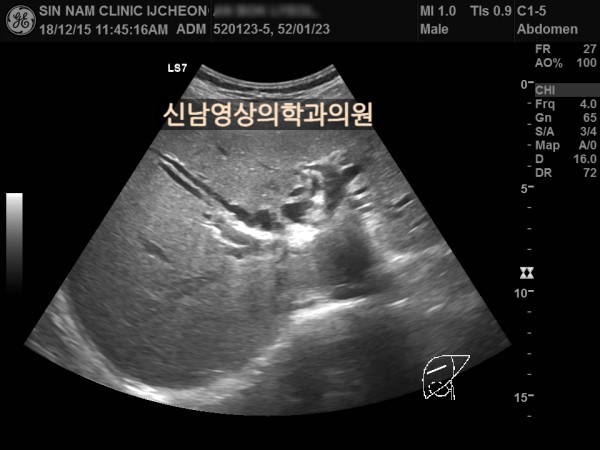

상복부 초음파 적용 사례

본 환자분은 50대 중반의 남성분으로 손가락안이 가렵다는 느낌으로 내원하셨습니다.

담도암과 담관암은 같은 질환을 지칭하는 용어로 간에서 만들어진 담즙이 십이지장으로 이동하는 통로인 담관에 발생하는 악성 종양입니다.

이 암은 간 안에 생기는 간내 담관암과 간 바깥에 생기는 간외 담관암으로 나뉘며, 가장 흔한 증상으로 통증이 없는 황달, 짙은 소변, 옅은 변, 복통, 체중 감소, 소양증 등이 나타날 수 있습니다.